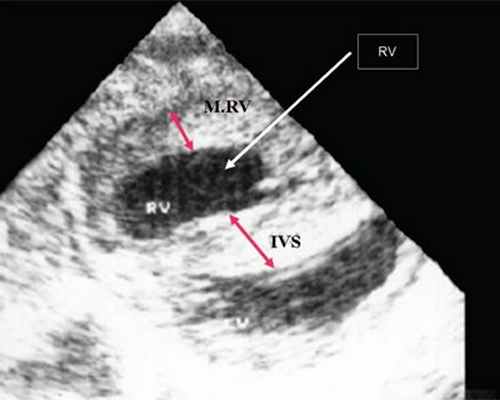

Нагрузка сопротивлением возникает при ситуации, когда выброс крови из желудочков сердца в магистральные сосуды затруднен на уровне полулунных клапанов (стеноз аорты и легочной артерии), подклапанного пространства (идиопатический гипертрофический субаортальный стеноз, подклапанный стеноз аорты или легочной артерии), на протяжении сосудистого русла (коарктация аорты) либо при значительном увеличении выходного сопротивления (синдром Эйзенменгера). В результате затруднения выброса крови резко возрастает напряжение миокарда соответствующего желудочка при относительно стабильном объеме крови, что служит проявлением систолической перегрузки сердца. При систолической перегрузке желудочков сердца независимо от нозологической формы порока полость желудочка, несущего основную нагрузку сопротивлением, умеренно увеличивается в размерах. В ответ на нагрузку сопротивлением на эхокардиограмме выявляется гипертрофия миокарда соответствующего желудочка, и чем больше сопротивление выбросу, тем резче выражена степень гипертрофии миокарда соответствующего желудочка и межжелудочковой перегородки (рис. 1) [3].

Рис. 1. Систолическая перегрузка правого желудочка. Поперечное сечение желудочков сердца при стенозе легочной артерии. Градиент давления правый желудочек - легочная артерия равен 200 мм рт.ст. Выраженная гипертрофия межжелудочковой перегородки и миокарда передней стенки правого желудочка.